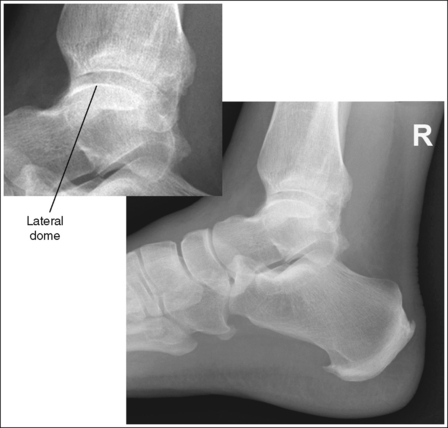

• Talar domes. The domes of the talus are formed by the most medial and lateral aspects of the talar's trochlear surface. On a lateral foot projection, they appear as domed structures that articulate with the tibia. On a properly positioned lateral foot projection, the talar domes should be superimposed and appear as one and the tibiotalar joint should be open. When the lateral foot is mispositioned, the domes are individually demonstrated, and they obscure the tibiotalar joint. Proximal-distal misalignment of the domes results from poor knee and lower leg positioning, and AP misalignment of the domes results from poor foot positioning.

• Effect of lower leg and knee positioning on proximal-distal talar dome superimposition. Often, if the knee is not fully extended (Figure 6-28) or if the distal tibia is not elevated to place the lower leg parallel with the IR in patients with large upper thighs, the proximal tibia is positioned farther from the imaging table than the distal tibia. The resulting image demonstrates the lateral talar dome proximal to the medial talar dome, the height of the longitudinal arch appears less than it actually is because the cuboid shifts anteriorly and the navicular bone moves posteriorly in this position, and the talocalcaneal joint will be narrowed (see Image 18). If the distal tibia is positioned farther from the table than the proximal tibia, the medial talar dome is demonstrated proximal to the lateral dome, the height of the longitudinal arch appears higher than it actually is because the cuboid shifts proximally and the navicular bone moves anteriorly in this position, and the talocalcaneal joint will be widened (see Image 19).

When viewing a lateral foot projection that demonstrates one of the talar domes proximal to the other, evaluate the height of the longitudinal arch and the degree of narrowing or widening of the talocalcaneal joint to determine which dome is the proximal dome. If the navicular bone is superimposed over more of the cuboid than expected and the talocalcaneal joint is narrowed, the lateral dome is the proximal dome; if the navicular bone is superimposed over less of the cuboid than expected and the talocalcaneal joint is wider, the medial dome is the proximal dome.

• Effect of foot positioning on AP talar dome superimposition. To demonstrate accurate AP alignment of the talar domes, position the lateral surface of the foot parallel with the IR. If this surface is not parallel with the IR, one of the talar domes is demonstrated anterior to the other. When the leg is rotated more than needed to place the lateral foot surface parallel with the IR, as shown in Figure 6-29, the medial talar dome is demonstrated anterior to the lateral talar dome (see Image 20). If the leg is not rotated enough to place the lateral foot surface parallel with the IR, as shown in Figure 6-30, the medial talar dome is demonstrated posterior to the lateral talar dome (see Image 21).

When viewing a lateral foot projection that demonstrates one of the talar domes anterior to the other, evaluate the position of the fibula in relation to the tibia to determine how to reposition the patient. On most lateral foot projections with accurate positioning, the fibula is positioned in the posterior half of the tibia. If the fibula is demonstrated more posteriorly than this relationship on a lateral foot projection with poor positioning, the medial talar dome is anterior and the patient was positioned with the forefoot depressed and the heel elevated (leg externally rotated), as shown in Figure 6-29. If the fibula is demonstrated more anteriorly than this relationship, the medial talar dome is posterior and the patient was positioned with the forefoot elevated and the heel depressed (leg internal rotation), as shown in Figure 6-30.